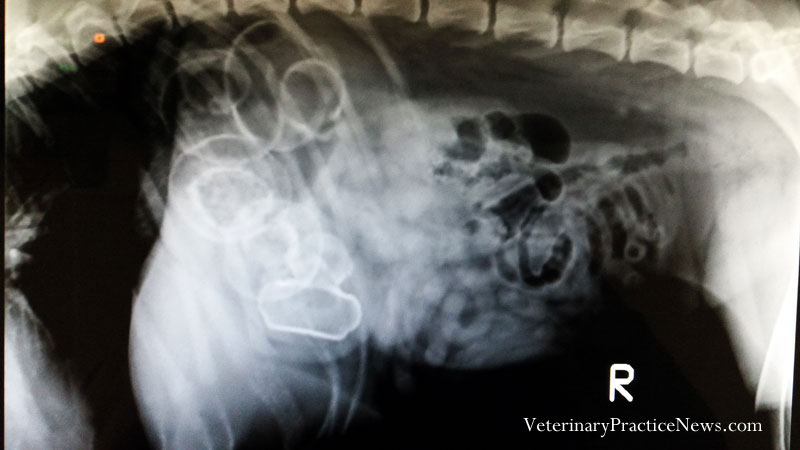

其他精采照片: